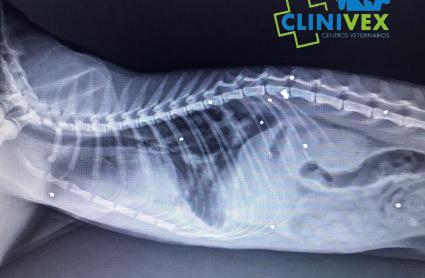

Su dueño denuncia que no es la primera vez que ocurre. Vive en una finca cercana al parque de Tres Arroyos y el lunes volvió a ver cómo uno de sus gatos enfermaba. Al llevarlo al veterinario, se descubrió que el animal había recibido 10 disparos de perdigones. Tenía, además, otro impacto antiguo que confirmó las sospechas de su dueño. Y es que otros 3 animales de los 10 que tenía han fallecido, y teme que haya sido por la misma causa. En este caso, al menos, el animal continúa con vida. El veterinario pudo salvarlo tras una operación, aunque continúa herido y podría necesitar nuevas intervenciones. El hombre ha denunciado el caso, y el Seprona se encuentra ya buscando al autor o los autores de los disparos.